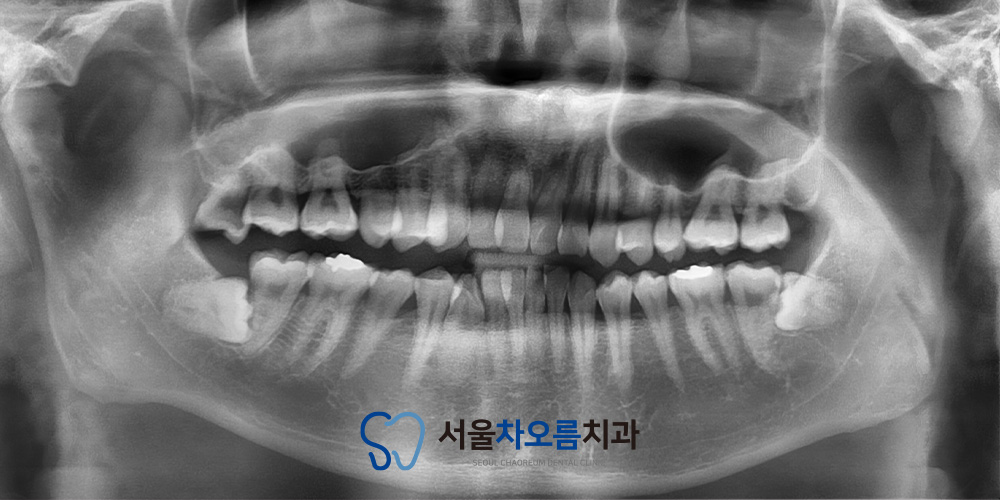

엑스레이 상에서는

하마종으로 인해 뼈나 주변 구조물에

별다른 이상이나 침범 소견은

관찰되지 않았습니다.

즉, 하마종이 연조직에 국한되어 있었으며

주요 구조에는 영향을 미치지 않은

상태로 확인되었습니다.